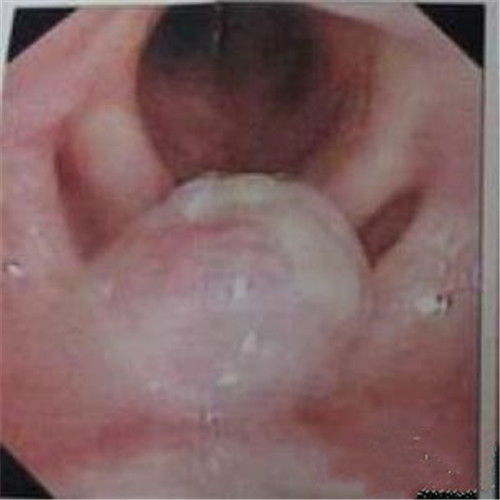

呼吸道感染者扁桃體發炎切除物

呼吸道感染口腔內部發炎

呼吸道感染兩側發炎